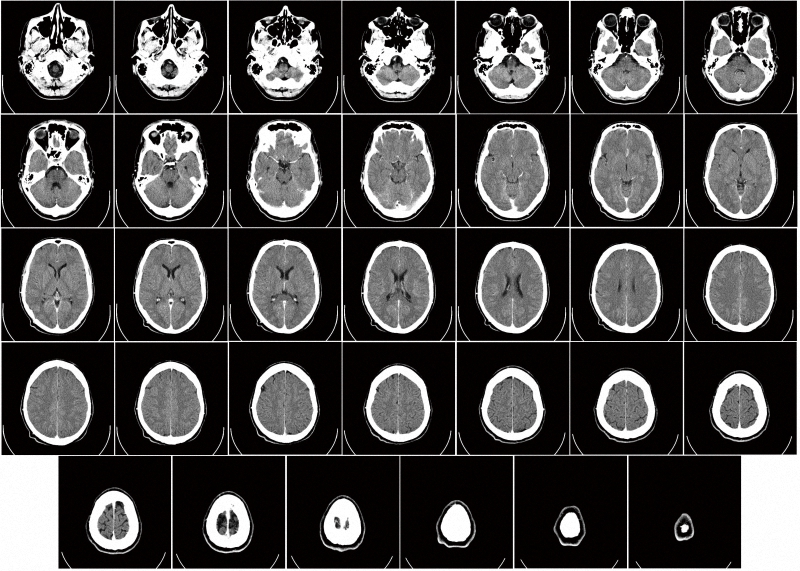

CT辐射最高 胸透基本取消

在我们日常能接触到的放射性检查中,CT(计算机断层扫描)类成像的辐射剂量最高。CT是一种三维放射线医学影像,主要通过单一轴面的X射线旋转照射人体。由于不同的组织对X射线的吸收(阻挡)能力不同,可以用电脑的三维技术重建出断层面影像,将所有断层影像层层堆叠,就形成了立体影像。这种技术优点在于影像分辨率高,可以全面而完整地观察到患处的情况,但也带来了不容忽视的受照剂量,个个都是“毫希级”的。一次盆腔CT带给人体的有效剂量达20毫希,心血管CT为9~12毫希、结肠镜CT为6~11毫希、胸部CT为7~8毫希、头部CT为1~2毫希。除了头部CT外,其他都已经明显超出了一年的平均剂量。

一次脑部CT成像大约贡献1~2毫希辐射